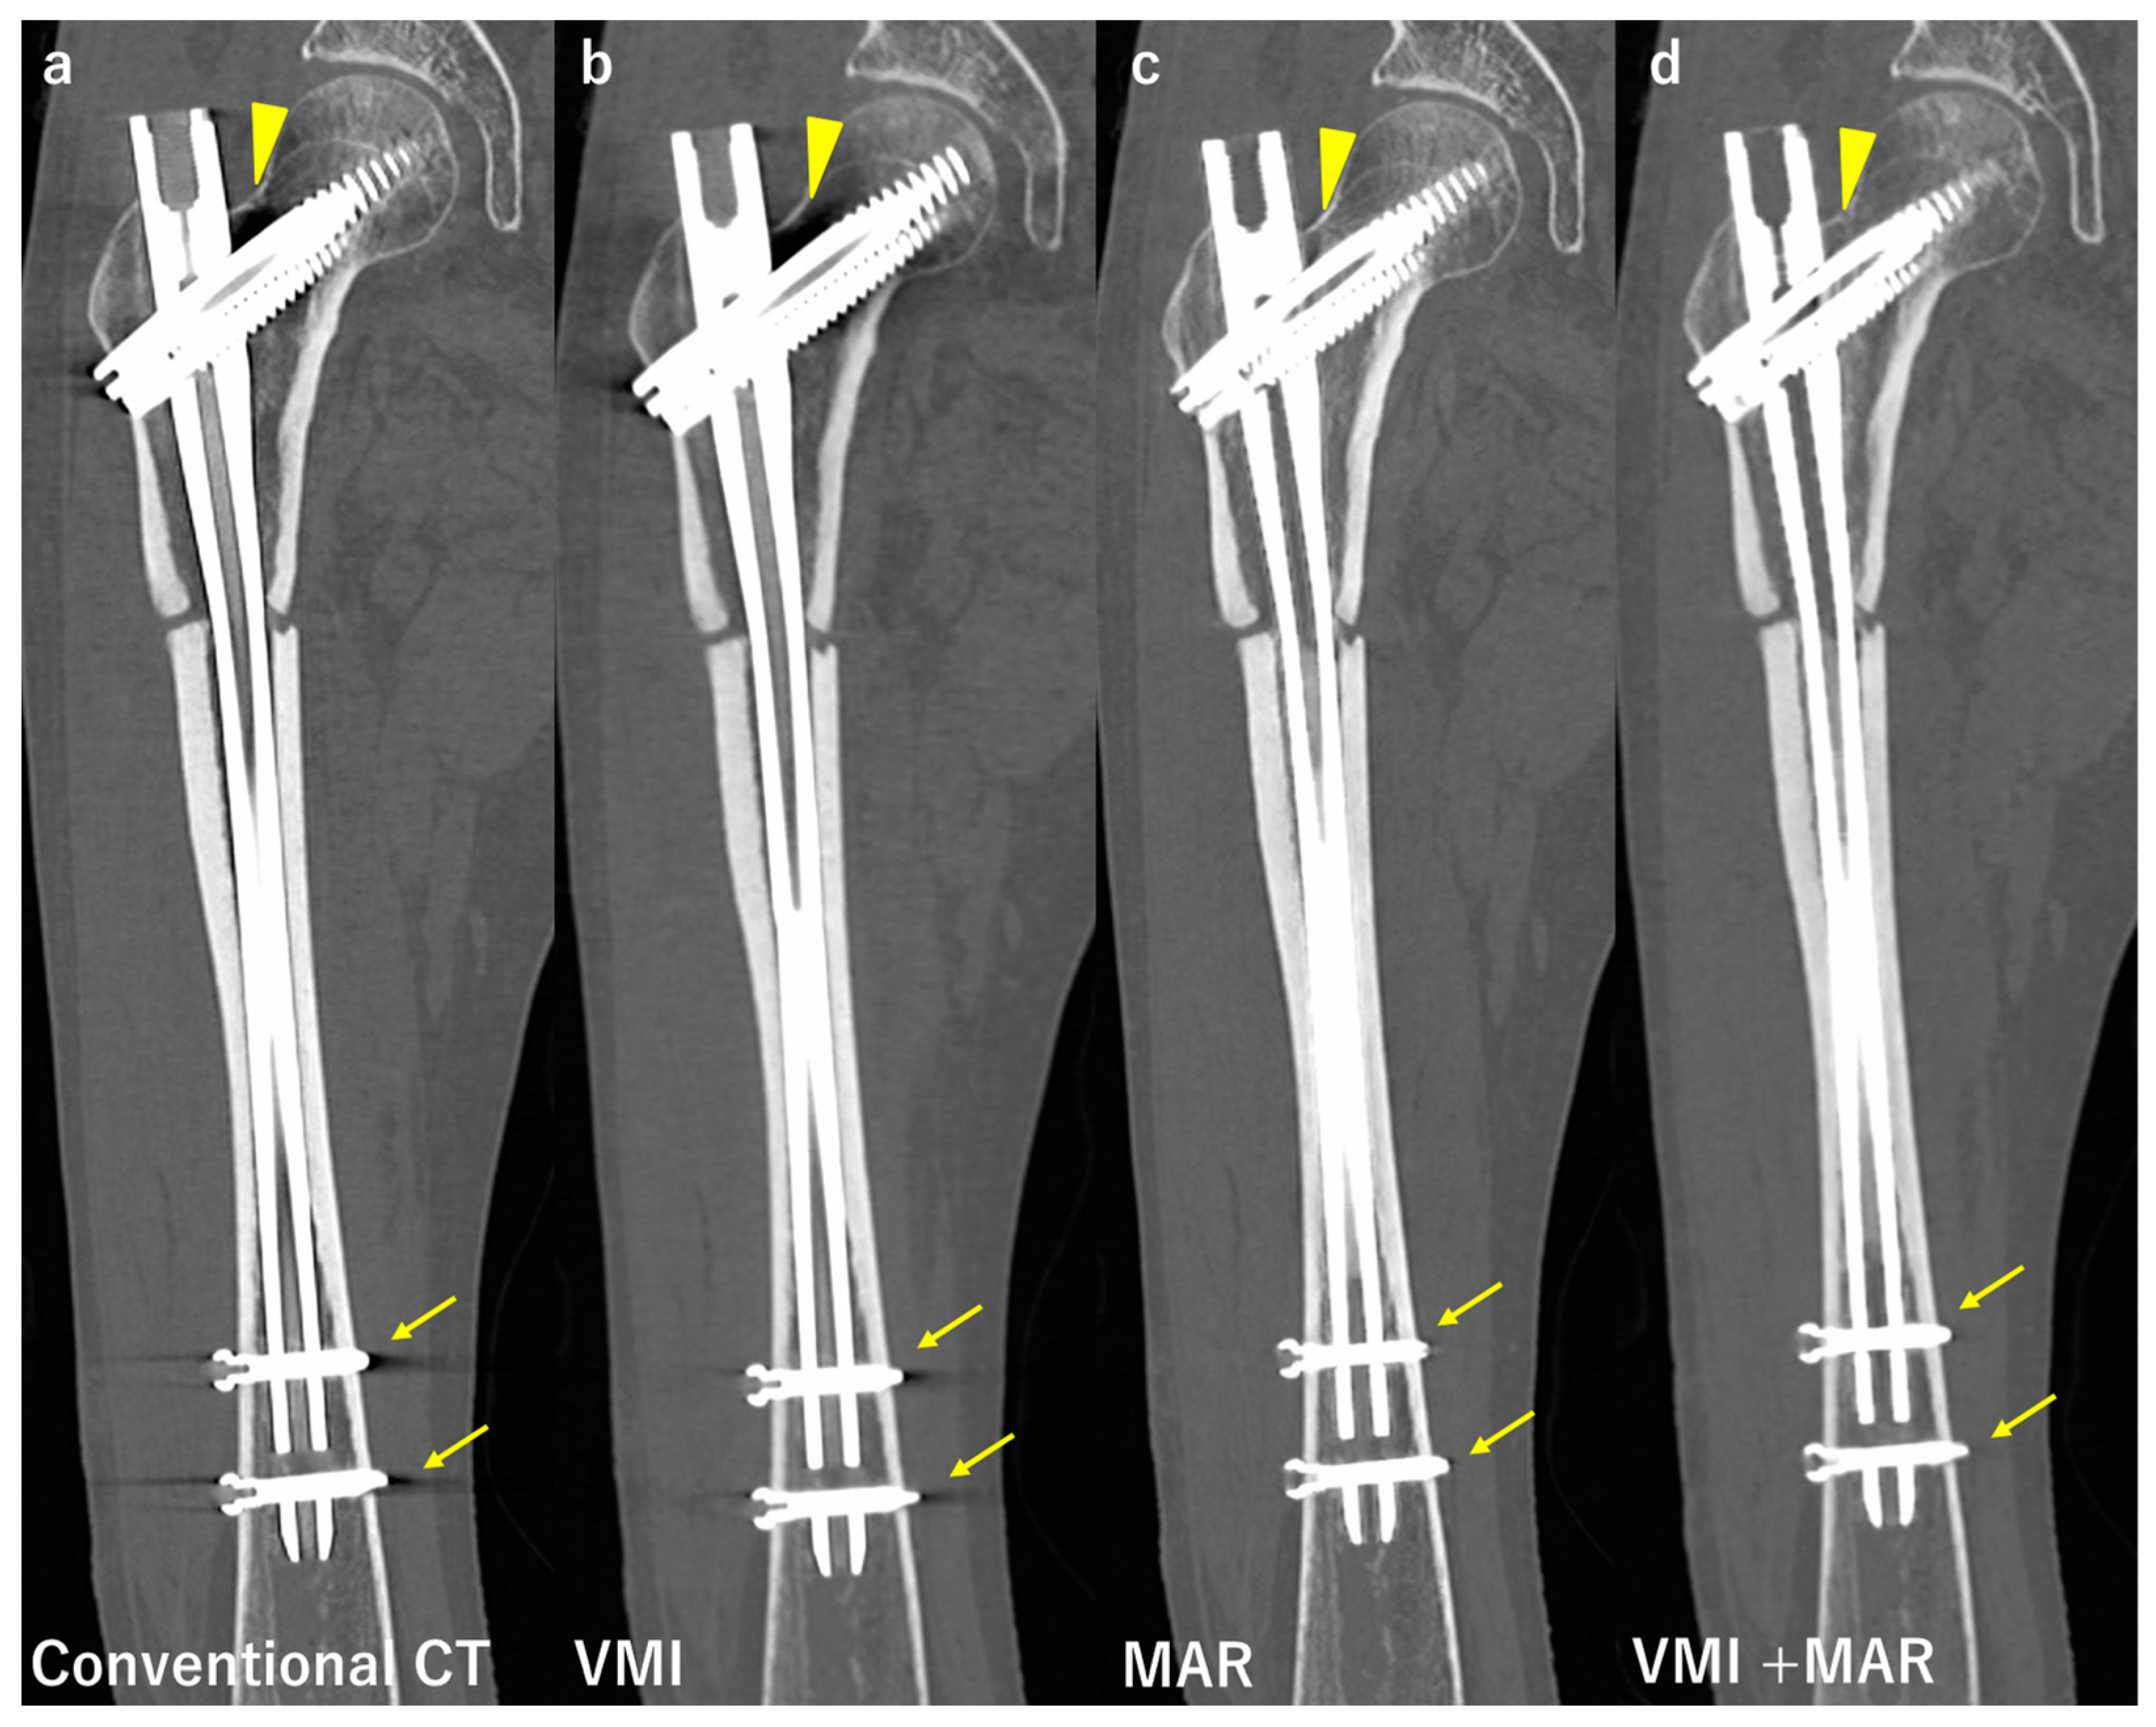

- Neuhaus, V.; Hokamp, N.G.; Zopfs, D.; Laukamp, K.; Lennartz, S.; Abdullayev, N.; Maintz, D.; Borggrefe, J. Reducing artifacts from total hip replacements in dual layer detector CT: Combination of virtual monoenergetic images and orthopedic metal artifact reduction. Eur. J. Radiol. 2019, 111, 14–20. [Google Scholar] [CrossRef]

- Bongers, M.N.; Schabel, C.; Thomas, C.; Raupach, R.; Notohamiprodjo, M.; Nikolaou, K.; Bamberg, F. Comparison and combination of dual-energy and iterative-based metal artefact reduction on hip prosthesis and dental implants. PLoS ONE 2015, 10, e0143584. [Google Scholar] [CrossRef]

- Long, Z.; Delone, D.R.; Kotsenas, A.L.; Lehman, V.T.; Nagelschneider, A.A.; Michalak, G.J.; Fletcher, J.G.; McCollough, C.H.; Yu, L. Clinical Assessment of Metal Artifact Reduction Methods in Dual-Energy CT Examinations of Instrumented Spines. Am. J. Roentgenol. 2019, 212, 395–401. [Google Scholar] [CrossRef]

- Yue, D.; Rong, C.F.; Ning, C.; Liang, H.; Lian, L.A.; Xin, W.R.; Hong, L.Y. Reduction of metal artifacts from unilateral hip arthroplasty on dual-energy CT with metal artifact reduction software. Acta Radiol. 2017, 59, 853–860. [Google Scholar] [CrossRef]

- Chae, H.-D.; Hong, S.H.; Shin, M.; Choi, J.-Y.; Yoo, H.J. Combined use of virtual monochromatic images and projection-based metal artifact reduction methods in evaluation of total knee arthroplasty. Eur. Radiol. 2020, 30, 5298–5307. [Google Scholar] [CrossRef]

| Neuhaus et al. [42] | Conventional CT, MAR, VMI, VMI + MAR | 24 patients after THA | VMI + MAR reduced artifacts the most. VMI + MAR improved the assessment of adjacent structures the most. |

| Andersson et al. [57] | Conventional CT, MAR, VMI, VMI + MAR | Bilateral hip prosthesis phantom | Artifact reduction rate MAR 52–75% VMI 12–52% (in a certain region artifact increased up to 32%) VMI + MAR 75–77% |

| Bongers et al. [58] | Conventional CT, MAR, VMI, VMI + MAR | Hip prosthesis and dental implants. Qualitative and quantitative evaluation. | Artifact reduction rate (Hip, dental implant, respectively) VMI 33%, 8% MAR 56%, 71% VMI + MAR 76%, 76% |

| Long et al. [59] | MAR VMI VMI + MAR | 20 patients with instrumented spines. Artifact score (1 to 5) Image quality score (1 to 4) | VMI + MAR showed the best artifact and image quality scores. ICC 0.779 |

| Yue et al. [60] | VMI VMI + MAR (80, 100, 120 and 140 kV) | 35 patients with THA. Artifact index (AI) CT number Subjective scores | AI in VMI + MAR at 120 and 140 kV were significantly lower than others. Accuracy of CT numbers for the peroprosthetic region improved with VMI + MAR. VMI + MAR at 120 and 140 kV had higher subjective scores. |

| Chae et al. [61] | Conventional CT MAR VMI VMI + MAR | 57 patients with TKA Area of the artifacts Mean attenuation Artifact index (AI) Contrast-to-noise ratio (CNR) | VMI + MAR showed the best performance in artifact reduction and soft tissue depiction. MAR depicted bony structures the best. |